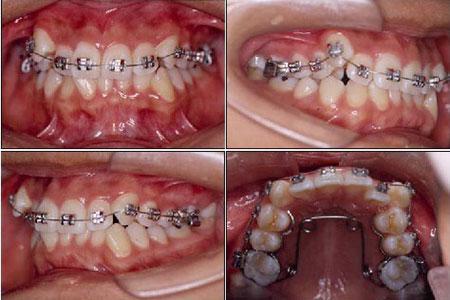

(1)固定矫治器:是目前应用广泛的矫治器。有方丝弓矫治器、直丝弓矫治器等,根据矫治器的质材又分为金属托槽矫正器、透明陶瓷托槽矫正器等。其矫治原理是将托槽、带环等一些固位装置粘附在每个牙齿上,各种富有弹性的钢丝、橡皮筋、弹簧等产生的力通 过固位装置传导给每个牙齿,使牙齿向预定的方向移动。此类矫治器因病人不能随意取下,而被称为固定矫治器。